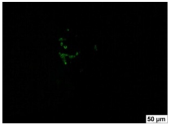

2.4. Evaluation of Macrophage Adhesion to the Surface of the Tested Samples

Following the investigation of cytotoxicity, the adhesion of macrophages to the surface of the examined samples was explored. In the experiments, it was observed that the number of adhered macrophages from the RAW 264.7 line on the surface of tablet wells without the investigated composite film materials in the microscope’s field of view was 355 ± 36 (Table 4). Upon placing RAW 264.7 cells in the tablet wells with the surface of the comparison sample “Seprafilm”, the number of adhered cells significantly decreased to 128 ± 16 within the microscope’s view field. The adhesion of macrophages on the surface of the composite film materials samples, based on the sodium salt of carboxymethylcellulose modified by allantoin (2, 3), did not differ significantly from the comparison sample “Seprafilm”.

The number of adhered cells in the microscope’s field of view was 215 ± 31 (p = 0.058) and 195 ± 29 (p = 0.064) cells, respectively. In contrast, the ability of macrophages to adhere in the samples of composite film materials based on glycoluril-modified sodium salt of carboxymethylcellulose (4, 5) was significantly lower than in sample (1) and the studied samples (2, 3). The number of adhered cells in the microscope’s field of view was 61 ± 8 and 18 ± 5, respectively.

Consequently, the tested composite film materials samples, which are based on allantoin-modified sodium salt of carboxymethylcellulose (2, 3), exhibit a diminished ability for macrophages from the RAW 264.7 line to adhere, and their adhesion value is comparable to that of sample (1).

The samples of composite film materials, derived from the glycoluril-modified sodium salt of carboxymethylcellulose (4, 5), exhibit notably reduced adhesion of RAW 264.7 line macrophages to the surface compared to both sample (1) and the examined composite film materials based on allantoin-modified sodium salt of carboxymethylcellulose (2, 3).

3.4. Adhesion of Macrophages to the Surface of the Tested Samples

Following the investigation of cytotoxicity, the adhesion of macrophages to the surface of the examined samples was scrutinized. Experimental results revealed that the number of adhered macrophages of the RAW 264.7 line on the surface of tablet wells lacking the investigated composite film materials within the microscope’s field of view was 355 ± 36 (Table 4). Upon placing RAW 264.7 cells in the wells of the tablet on the film surface of the comparison sample “Seprafilm”, the number of adhered cells significantly decreased to 128 ± 16 in the microscope’s field of view. The extent of macrophage adhesion on the surface of the samples of composite film materials based on allantoin-modified sodium salt of carboxymethylcellulose (2, 3) did not differ from sample (1), with the number of adhered cells in the microscope’s field being 215 ± 31 (p = 0.058) and 195 ± 29 (p = 0.064), respectively. The ability to adhere macrophages in the samples of composite film materials based on glycoluril-modified sodium salt of carboxymethylcellulose (4, 5) was significantly lower than in sample (1) and the studied samples (2, 3), with the number of adhered cells in the microscope’s field being 61 ± 8 and 18 ± 5, respectively.

Hence, the samples of the examined composite film materials based on allantoin-modified sodium salt of carboxymethylcellulose (2, 3) exhibit a limited ability to adhere RAW 264.7 macrophages, and their adhesion capability is not inferior to that of sample (1). In the case of samples of composite film materials based on glycoluril-modified sodium salt of carboxymethylcellulose (4, 5), the adhesion of RAW 264.7 macrophages to the surface is significantly lower compared to sample (1) and the investigated composite film materials based on allantoin-modified sodium salt of carboxymethylcellulose (2, 3).

The plates were subjected to a 24 h incubation at 37 °C in a 5% CO2 atmosphere. Following this, non-adherent cells were removed by resuspending the cell suspension. Cells attached to the surface of the composite film materials were subsequently fixed with 2.5% glutaraldehyde for 30 min and stained with fluorescent dyes, specifically Phalloidin-Atto-488 for cytoskeleton staining and DAPI for nucleus staining.

The count of cells adhered to the surface of the composite film materials within the microscope’s field of view was conducted utilizing a Leica DMi8 fluorescence microscope [40]. Three repetitions of experiments were carried out for each composite film sample and the comparison sample “Seprafilm”, with the number of adhered cells in each experiment assessed across three fields of view.